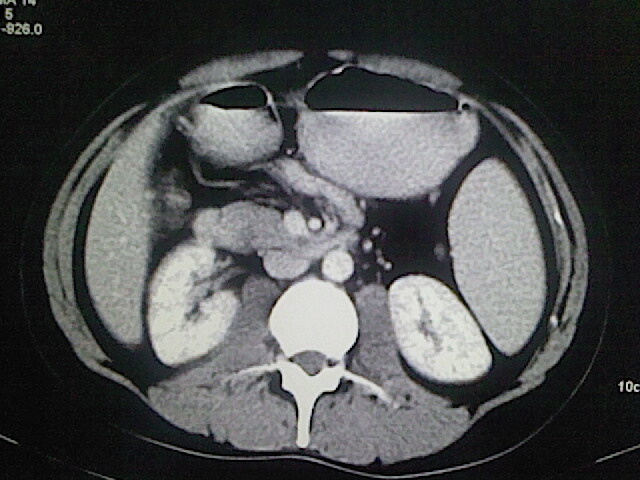

以下是引用卜一在2009-3-14 9:49:00的发言:[br]胆囊萎缩,胆囊壁不规则增厚,内部结构模糊,增强明显强化。另:肝左叶外侧段肝囊肿。支持:慢性胆囊炎!高度可疑:胆囊癌!

以下是引用余辉在2009-3-14 8:48:00的发言:[br]1)慢性胆囊炎。2)肝左叶外侧段肝囊肿。3)脂肪肝。[br]支持,胆囊萎缩,密度增高,不知b超具体有何提示,钙胆汁?结石?

以下是引用jiangjing在2009-3-14 10:18:00的发言:[br]1)慢性胆囊炎。2)肝左叶外侧段肝囊肿。3)脂肪肝。4.】建议行肝功能检查